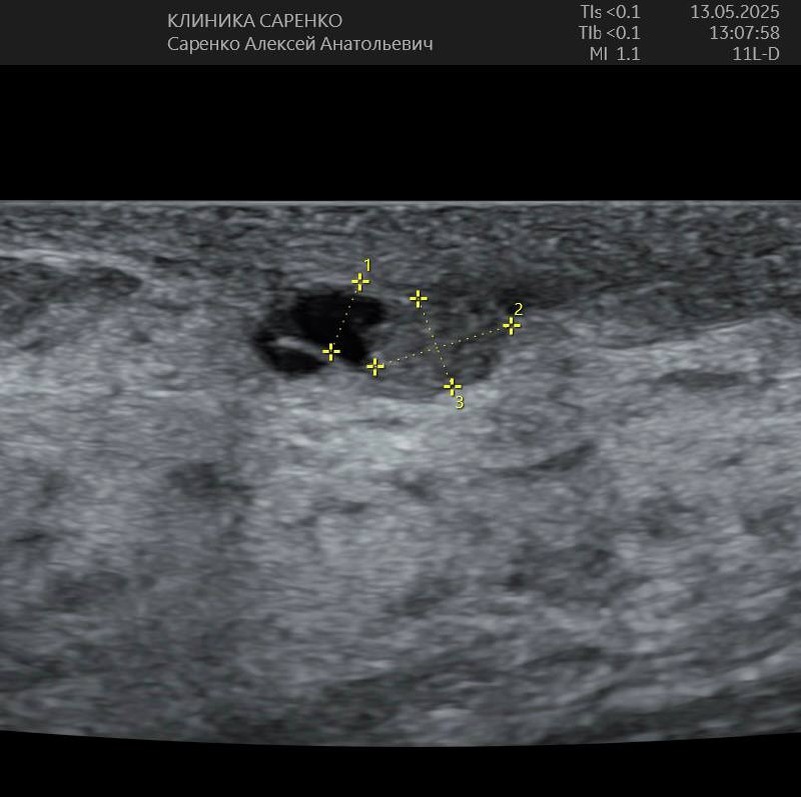

Внутрипротоковая папиллома молочной железы (болезнь Минца)

✅ Молодая женщина, жалоб нет

✅ На УЗИ обнаружили кисту в молочной железе, делали пункцию - всё хорошо

🟢 Два года наблюдается, делается УЗИ

✅ Видят черный овал, значит киста - домой

✅ Но это не киста, это проток и в нём папиллома!

✅ Отправил на консультацию к моему любимому маммологу Белозерцевой.

✅ Пункция - папиллома с атипичными клетками!

✅ Удалили, далее будем наблюдать